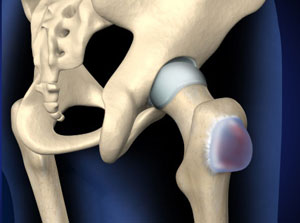

Здоровье суставов: Трохантерит и его влияние на мышцы